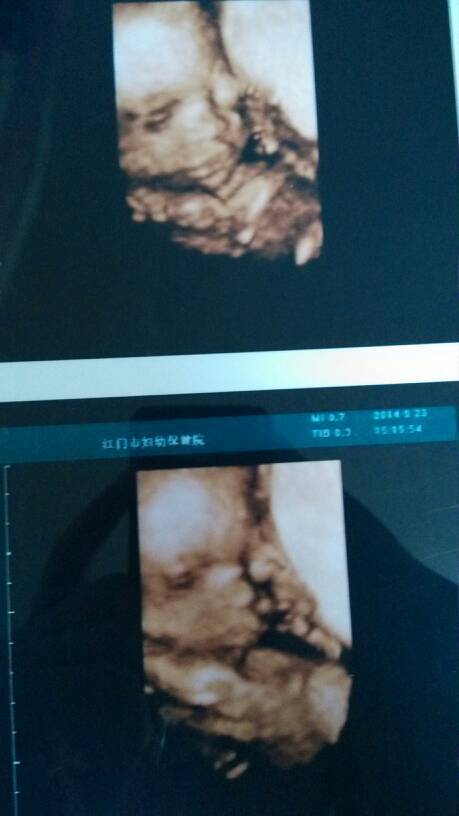

这是今天做的三维,宝宝一切顺利,就是比孕期少了一周,帮我看看宝宝有一边眼睛那里是什么东西

你好,胎儿只是偏小一周的情况,这个问题不是很大的,你平时多吃一点蛋白质和钙质含量丰富的食物就行

那里没事的,宝宝在肚子里都这样的